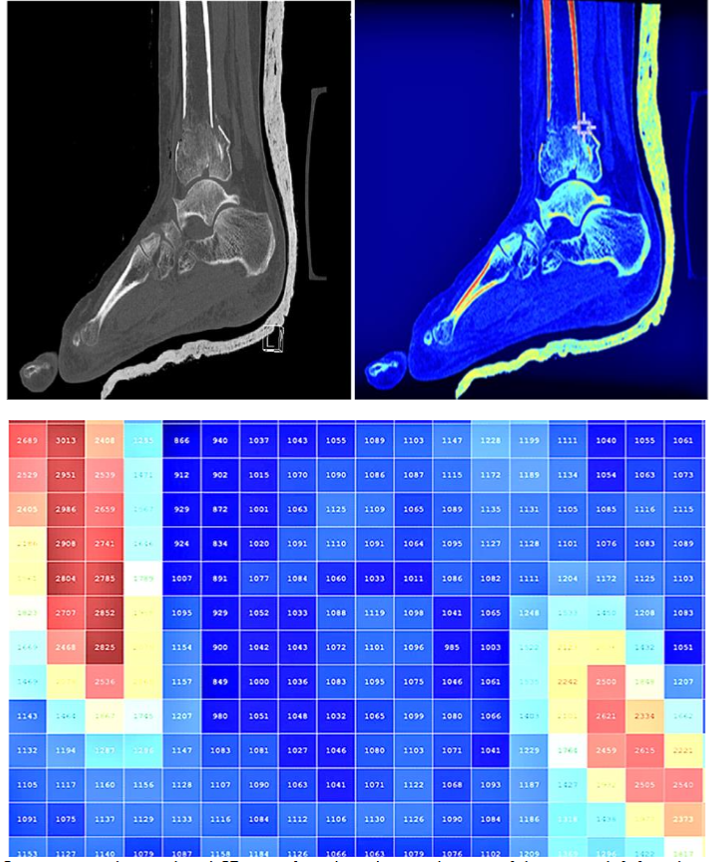

A 54-year-old female was admitted to the A&E department at ADAN Hospital following high-impact trauma. Non-enhanced Multi-Detector Computed Tomography (MDCT) images of the left foot, acquired using a GE Revolution GSI CT, demonstrated the extent of the injury. The images were captured with a 120 kVp, Smart mA range (312-370), a slice thickness of 1.25 mm, a 50 cm SFOV, 0.984 pitch, and an exposure time of 500 ms. The images suggested a comminuted fracture involving the distal tibia and fibula, with intra-articular extension into the tibiotalar articulation.

We developed a pixelated Quantitative Colour CT Density Map (QCTDM) which is a colour visualization technique built upon data collected from a CT scan of the left foot using MATLAB software to display data in small, discrete units or pixels, each of which corresponds to a specific Hounsfield Unit (HU) value, and to set accurate threshold values for generating a 3D model: bone (124-1626), soft tissue (-700 to 225), fat (-205 to -51), and compact bone (662-1626). The fracture pattern suggested significant complexity, with the potential for misalignment and compromised joint function if not properly addressed. The pixelated QCTDM of a selected sagittal image clearly displayed various density levels of the selected region.

Materialize Mimics Care Suite Research which uses advanced algorithms to process imaging data and reconstruct precise anatomical structures, was then utilized to generate an unrestricted 360-degree viewing model of the foot in a virtual reality environment, allowing for detailed visualization of the shattered ankle bone and its localization, including separation of muscles, soft tissue, and fat. The software also includes features for the integration of virtual reality (VR) and 3D printing, allowing for preoperative rehearsal and the creation of physical prototypes of the anatomy. The QCTDM display provided an effective platform to produce a 3D global view, indicating the optimal locations for the application of fixing screws to avoid loosening post-internal fixation.